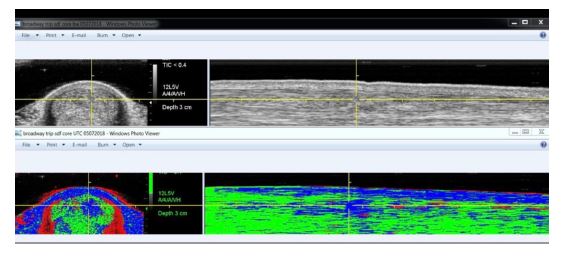

Example The below example shows how difficult it is to assess scarred tissue in the tendon using ultrasound only. It is only after using UTC technology, the large scared (type II, Blue fibres) are clearly visible. This horse was planned to go back into training. The fact that there is already “tearing” at the scar (red fibres dotted around the scar) indicates this horse is clearly not ready for training.